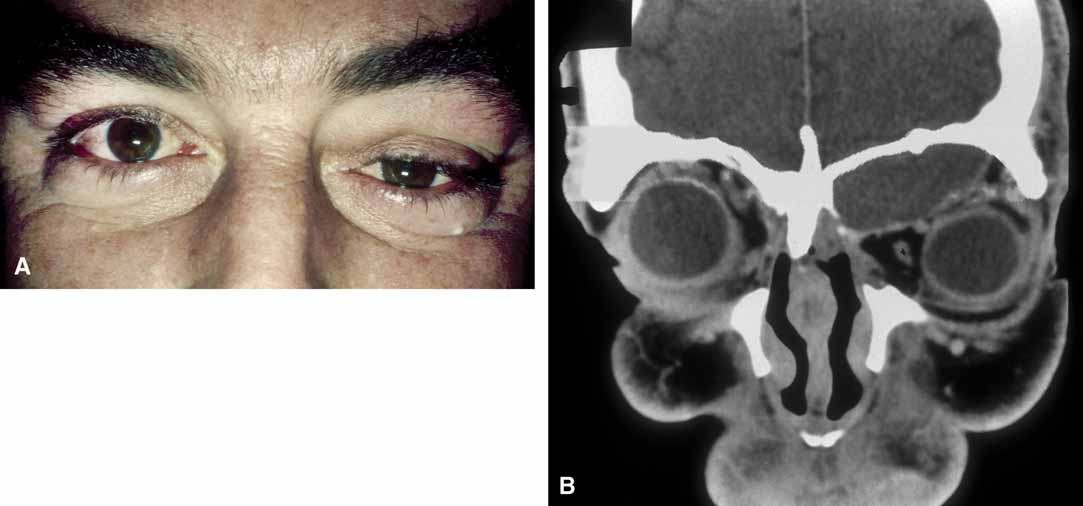

Failure of the fetal fissure to close at 4 weeks of development results in proliferation of neuroectoderm through the opening, leading to formation of an orbital cyst. In almost all cases, the resulting eye is defective, smaller than normal, and has an attached cystic mass at birth.25,26 The cyst may be smaller or larger than the eye; its appearance is dependent on the size of the ocular defect and its rate of expansion; microphthalmos with a cyst may be bilateral.27–29 The cyst is slate blue and translucent, and may displace the globe (Fig. 7).

Fig. 7 A. Microphthalmos with cyst in a newborn with congenital facial cleft abnormality. B. Computed tomogram shows globe communication with the cyst cavity; normal anterior segment structures are absent.